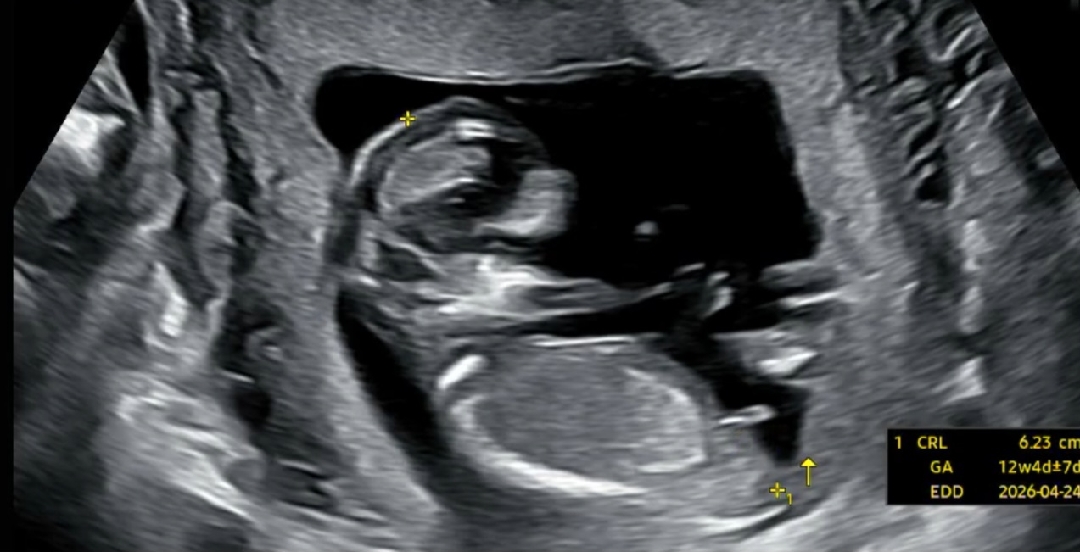

13주차 초음파 각도법!!

각도법으로 보면 전 아들같은데 다른분들은 딸같다고하네요!! 딸일까요? 아들일까요?